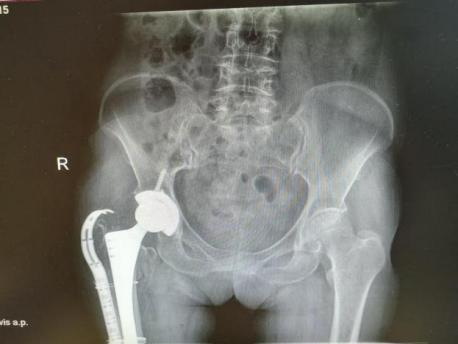

12月17日,贵州航天医院第88次晨读会由我院骨一科主任、副主任医师陈明勇作学术交流,他以“肱骨近端骨折并肩关节脱位的手术治疗”为题,全面讲解了该损伤的手术策略、术中血供保护理念及内侧支撑重建技术等内容,并通过多个典型病例图文资料分享了从损伤机制分析、手术步骤实施到术后随访评估的完整过程与关键细节,为临床处理此类复杂骨折提供了较为全面的技术参考,有助于在手术规划中结合个体情况开展针对性治疗。 贵州航天医院 骨科专家简介 陈明勇 骨一科主任,副主任医师 临床擅长:从事创伤骨科工作约20年,对骨缺损、骨不连、骨肿瘤、肢体畸形等的肢体矫形重建及功能重建,慢性化脓性骨髓炎的根治治疗、糖尿病足的保肢治疗、快速康复理念(ERAS)下的老年骨折的诊治,四肢复杂骨折的诊治,四肢骨折等微创手术治疗具有丰富的临床经验。 2004年毕业于遵义医学院临床专业,曾在中国人民解放军总医院、广西医科大学第一附属医院、上海第六人民医院骨科进修。中国中西医结合学会骨伤科专业委员会横向骨搬移治疗糖尿病足及微血管网再生学组首届委员,遵义市医学会创伤分会常务委员。 瞿 晖 骨科党支部书记,骨二科主任,副主任医师 临床擅长:对骨科的常见病、关节外科、脊柱外科及运动医学疾病的诊治具有丰富的临床经验,熟练掌握骨科手术操作技术。 毕业于遵义医学院临床医学系,2005年前往广州中山大学第一附院骨显微医学部进修学习,2011年前往成都华西医院进修学习,并多次在省内外学习骨科相关知识,是中华医学会骨科分会会员。 赵小锋 中共党员,骨二科副主任,副主任医师 临床擅长:从事骨科临床工作11年,对骨科常见病、多发病诊疗有较为丰富的临床经验,擅长脊柱相关疾病诊断及治疗,尤其是颈、腰、腿疼痛疾病诊断及治疗,擅长胸腰椎骨折微创经皮穿刺内固定术、经皮穿刺椎体成形术、经皮穿刺脊柱内镜下腰椎间盘摘除术、单纯开创腰椎间盘摘除术、腰椎滑脱复位椎间植骨椎融合内固定术、腰椎管狭窄减压融合内固定术及人工髋、膝关节置换术等。 2012年毕业于遵义医学院外科学专业硕士研究生,2019年参加“遵义市115医学人才精英计划”于上海交通大学第一附属医院培训学习,2023年于北京大学第三人民医院脊柱外科进修学习,曾获得遵义市优秀医师荣誉称号。 遵义市手外科第一届委员,遵义市医学会创伤分会第一届委员,遵义市医学会创伤分会第二届委员,贵州省康复医学会第三届脊柱脊髓专业会委员,遵义市医学会烧伤与整形外科学分会委员,发表论文5篇,其中国家级核心期刊1篇,SCI论文1篇,主持市级课题1项并结题,参与市级课题2项。 赵兴东 骨科主任医师 临床擅长:擅长骨科的常见病及各种创伤、四肢骨折创伤修复、骨感染、手足疾病的诊治和手足体表畸形的矫形整复,熟练掌握骨科四肢骨病及创伤的手术操作技术,尤其在四肢关节复杂性损伤、手足外伤、组织缺损创面、难治创面的皮瓣修复方面及平足、高弓足矫形方面及四肢慢性疼痛诊治、康复方面具有丰富的临床经验。 硕士研究生,毕业于遵义医学院临床外科系,2015年前往山东省立医院手足外科进修学习;遵义市医学分会创伤分会第一、二届委员,遵义市手外科医学会第二委届员会常务委员;在省级及省级以上期刊发表文章9篇,参编著作2部,参与主持并完成市级课题1项,参与市级课题2项、省级课题1项。 张艳金 中共党员,骨科副主任医师 临床擅长:从事骨外科工作16年,对复合伤、多发伤的救治、四肢骨干骨折、关节周围骨折、骨肿瘤、骨髓炎等诊治具有丰富的临床经验。 中共党员,硕士研究生,2006年本科毕业于山西医科大学第二临床医学院,2011年研究生毕业于北京军区总医院;在“老年COPD患者合并髋部骨折的诊治”国际合作课题组研究两年,在老年髋部骨折的诊治方面具有丰富的经验,并发表论文6篇;主持遵义市级课题1项,承担遵义医科大学的临床教学工作,获得遵义医科大学优秀带教老师荣誉。编撰有《骨科疾病诊疗精粹》一书,开展2项新技术,编撰地方规范《务川自治县创伤骨科常见疾病诊疗规范》一书。 张俊凯 骨科副主任医师 临床擅长:从事骨科临床工作28年,对创伤骨折、骨感染、骨缺损、骨不连等外科诊治,四肢骨折的微创手术治疗,四肢复杂骨折(如关节内粉碎性骨折、多发骨折等)的损伤控制及手术治疗等具有丰富的临床经验。 1995年毕业于遵义医学院临床专业,2009年前往复旦大学附属医院骨科进修1年。 卢懿明 中共党员,骨科副主任医师 临床擅长:从事骨科工作18年,对创伤骨折、四肢骨折的微创手术治疗、四肢复杂骨折(如关节内粉碎性骨折、多发骨折等)的损伤控制及手术治疗,尤其是髋部骨折的PFNA等微创技术,踝关节骨折、膝关节周围骨折的Mipo微创技术等具有丰富的临床经验,开展了4项新技术,发明6项新型专利技术。 2005年毕业于遵义医学院临床专业,2017年,前往南方医科大学第三附属医院骨科进修半年,回院后运用Mipo技术对骨干骨折及干骺端骨折的治疗技术,同时积极开展骨盆骨折、髋臼骨折腹直肌外侧切口的应用;发表了多篇专业论文,经常参与省内外学术交流会授课,获得医院荣誉称号多个。 邬夏荣 骨科副主任医师 临床擅长:从事骨科工作16年,对四肢复杂骨折、骨肿瘤的诊治,尤其是足踝创伤、慢性踝关节损伤、平足症等诊疗具有丰富的临床经验。 2006年毕业于遵义医科大学临床医学专业,曾在陆军军医大学西南医院进修学习,发表多篇骨科学术论文。 余德怀 中共党员,骨科副主任医师 临床擅长:从事骨科工作10余年,对运动医学、骨关节、脊柱外科常见病、多发病的诊治具有丰富的临床经验。 硕士研究生,2011年毕业于遵义医学院临床医学专业,曾前往遵义医科大学附属医院运动医学专业进修学习;是贵州省医学会运动医学分会青年委员,西部关节镜联盟委员;发表多篇骨科学术论文。 冯 乾 骨科副主任医师 临床擅长:从事骨科工作近20年,熟练掌握骨科多发病及常见病的诊治,尤其对脊柱退变性疾病的诊断及治疗具有丰富的临床经验,主要研究脊柱微创相关治疗方式,能熟练开展椎间孔镜及UBE。 曾前往北京大学第三医院进修学习疼痛及椎间孔镜、首都医科大学友谊医院专业进修脊柱内镜;是贵州省康复医学会第三届脊柱脊髓专业委员会委员;发明专利3项、发表脊柱外科专业论文多篇。 贵州航天医院骨科简介 基本情况 贵州航天医院(原3417医院)骨科组建于1968年,前身是以创伤和断肢(断指)再植闻名于世的上海市第六人民医院骨科,中国断肢(断指)再植的奠基者、中科院院士陈仲伟等专家莅临科室指导医疗和教学,并在70年代开展了贵州省首例断肢(断指)再植手术。组建50余年来,诊治患者已逾百万,挽救了无数的伤病员,成为了保障遵义地区人民群众健康的重要支撑。 经过几代人的不懈努力,今天的骨科,已由创伤骨科发展至骨病、骨肿瘤、骨结核等领域,现有脊柱外科、关节外科、四肢创伤、手足外科四个亚专科,成为了集医疗、教学、科研于一体的综合学科,是贵州省临床重点专科、遵义市临床重点专科、遵义市骨科临床医学中心、遵义市基层骨科专科联盟理事长单位。 科室目前开放床位110张,共有医护人员50余人,副高级以上专家18人,硕士研究生15人。拥有一流骨科医疗设备多台,每年不定期选派优秀技术骨干到全国各大知名医学院校进修、学习、参观、交流,并邀请国内、国外知名专家教授来院进行交流、指导,通过不断引进国内外先进的诊疗技术,科室医疗技术水平稳步提升,为广大人民群众提供了优质的医疗服务。 专科特色 骨一科 (一)骨缺损、骨不连的肢体与功能重建 胫骨横向骨搬移技术治疗糖尿病足: (二)慢性骨髓炎的根治治疗 (三)肢体缺血性疾病如糖尿病足、脉管炎的保肢治疗 (四)皮瓣修复 (五)复杂创伤的治疗 (六)老年髋部骨折及小儿骨折快速手术 老年髋部骨折: 骨二科 (一)胸腰椎骨折微创经皮椎弓根螺钉固定术 (二)老年性骨质疏松性患者腰椎滑脱脊柱内固定术(骨水泥螺钉) (三)V形双通道脊柱内镜技术(VBE)腰椎融合术治疗腰椎退行性疾病 (四)老年性骨质疏松性骨折(PVP/PKP)术 (五)人工髋关节置换术 (六)双侧股骨头坏死人工全髋关节置换 (七)右侧全髋置换术后假体周围骨折翻修 (八)人工膝关节置换术 (九)人工膝关节假体松动翻修 (十)关节镜技术 传统手术切口 关节镜技术切口 诊疗范围 骨一科 1.四肢创伤、矫形。 2.手、足踝外科。 骨二科 end